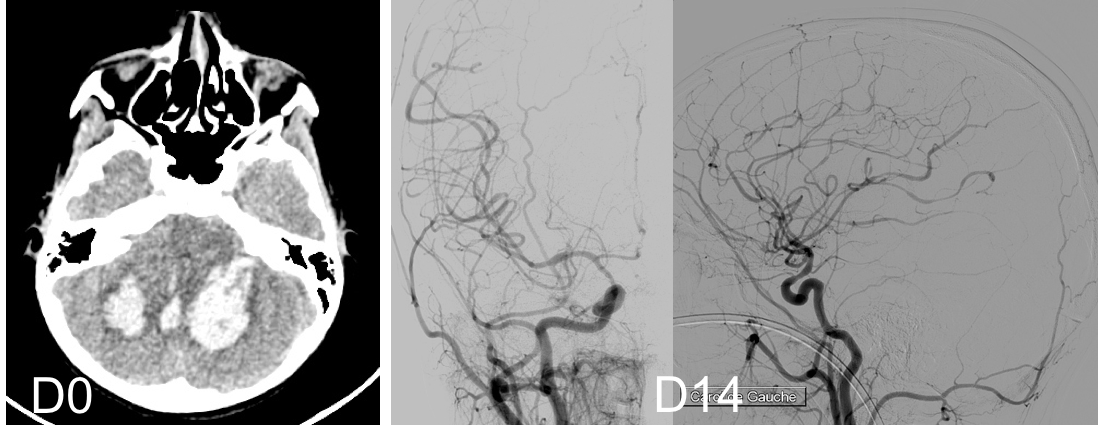

le saignement peut être favorisé par un effort physique, mais la majorité survient sans cause particulière voire pendant le sommeil. le risque de resaignement est estimé à environ 10% dans l’année qui suit. les MAV les plus agressives, celles qui tuent le plus, sont situées dans le cervelet.

la majorité des MAV de l’enfant se révèlent en effet par une rupture hémorragique, qui survient « comme un coup de tonnerre dans un ciel serein », avec céphalées, vomissements, déficit et troubles de conscience progressifs, parfois signes d’engagement. dans notre série, 78% des patients se présentaient avec une MAV rompue, 43% étaient comateux

classiquement lié à l’hémorragie méningée anévrysmale, le vasospasme peut également survenir après hémorragie cérébrale par rupture de MAV ; il semble néanmoins obéir à des mécanismes particuliers comme le montre sa topographie souvent inattendue. le traitement par inhibiteur calcique, qui n’a pas d’AMM chez l’enfant ni en dehors de la rupture anévrysmale, peut être malgré tout nécessaire.

le resaignement

il survient rarement dans les jours qui suivent l’hémorragie ; il représente cependant une menace tant que la MAV n’est pas totalement éradiquée

contrairement à l’adulte, il existe un risque de récidive d’angiome même si l’angiographie de contrôle semblait normale. Ceci est lié à l’immaturité des vaisseaux qui sont capable de produire de nouveau une MAV. Il est prudent de recontrôler l’angiographie à la fin de la croissance avant de déclarer le patient guéri.